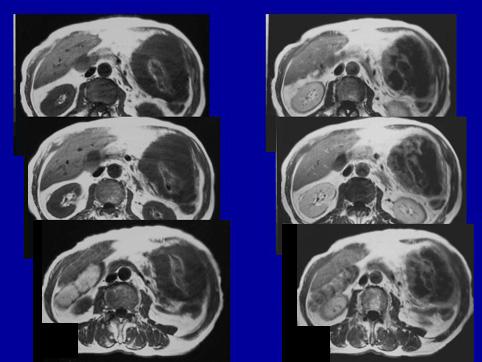

Adenocarcinoma Anaplástico , en que se ve Necrosis en gran escala

Tumor Epitelial Maligno/Adenocarcinoma

parte(separada por órganos)

método de exámen

TAC

Tipo 3(Tipo ulcerado de bordes infiltrados)/

diámetro mayor del tumor

40 -

grado de penetración

s(a)